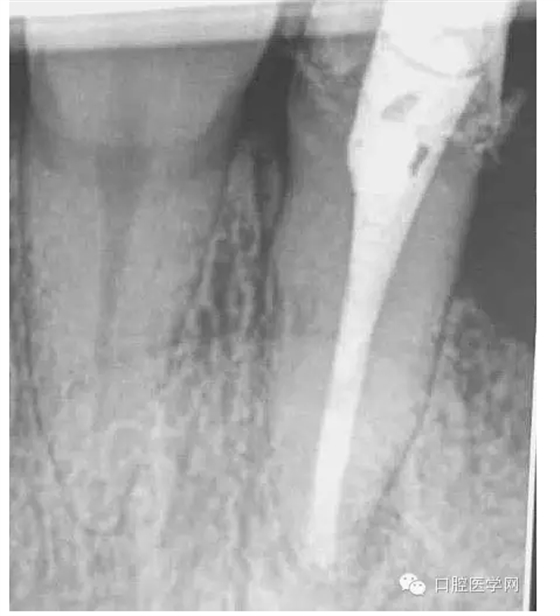

一年前接診的病例,在各級(jí)門診診所轉(zhuǎn)診三次,不見好轉(zhuǎn)。最后到本院 !觀察一年以后的效果!

5.待MTA凝固后進(jìn)行熱牙膠充填。